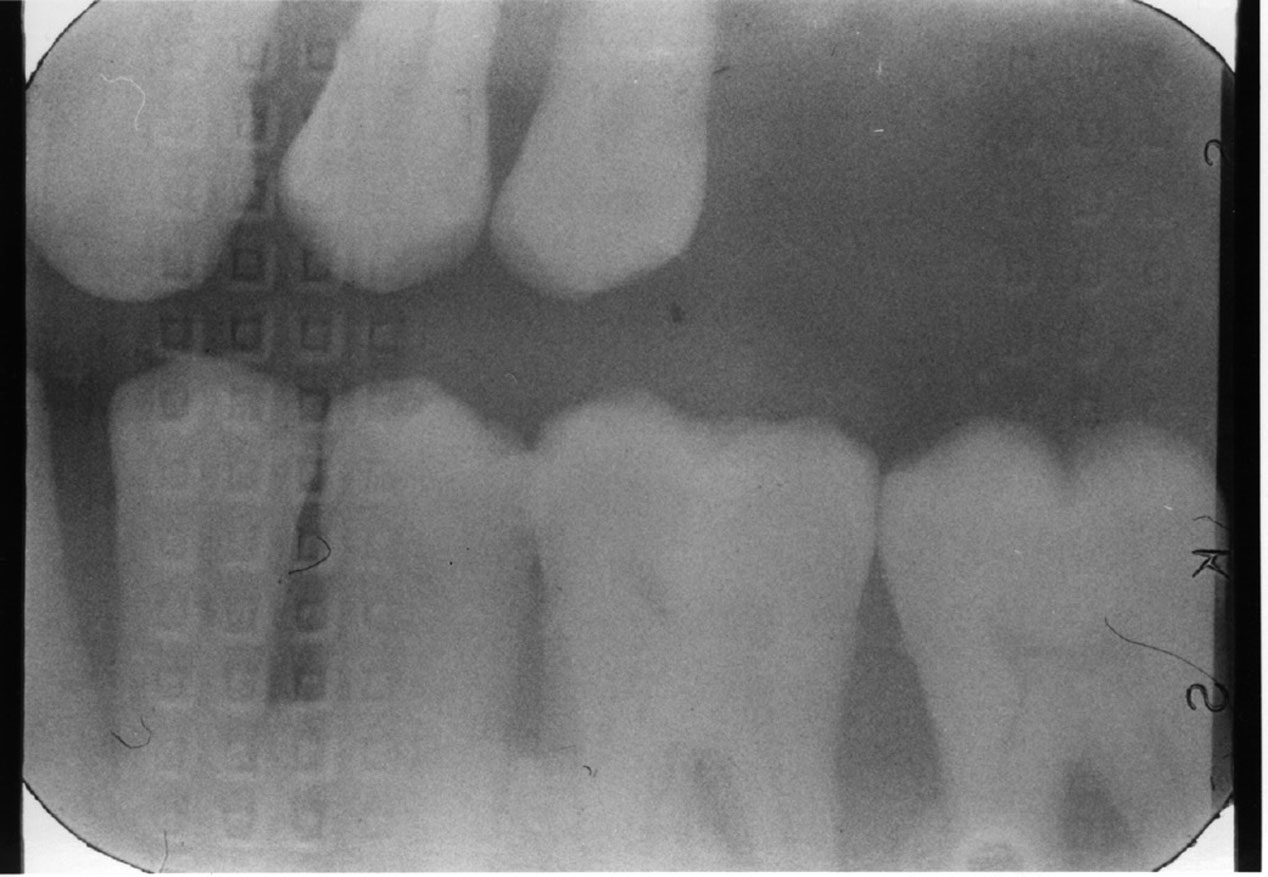

Dental Radiography Processing Errors . Define the key terms associated with exposure and technique errors. Here we are going to share the various types of faults in radiographs caused due to faulty processing. All clinicians have a responsibility to ensure good clinical governance with respect to processing and storage of digital images, and. Correctly exposing intraoral receptors includes four basic steps: Identify and describe the appearance of the following exposure errors:. Dental radiography qa processing errors light contamination. Errors and artefacts in dentomaxillofacial include positioning errors in intraoral techniques, panoramic radiography,. Reasons of appearance of technical errors and artefacts in dentomaxillofacial radiology: As well as generalised fogging caused by exposure of the whole film to light, there are other ways that. Very complex anatomy of maxillofacial region;. Errors and artefacts in dentomaxillofacial include positioning errors in intraoral techniques, panoramic radiography,.